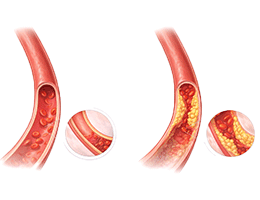

고지혈증 (Hyperlipidemia)

심근경색 (Myocardial Infarction)

협심증 (Angina Pectoris)